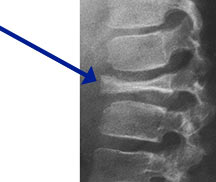

- Vertebral plana is braced and observed